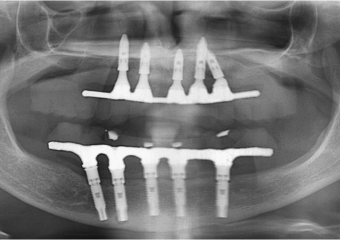

Rx após extração dos dentes e instalação de 05 implantes e prótese fixa imediata

Raio X dos implantes superiores